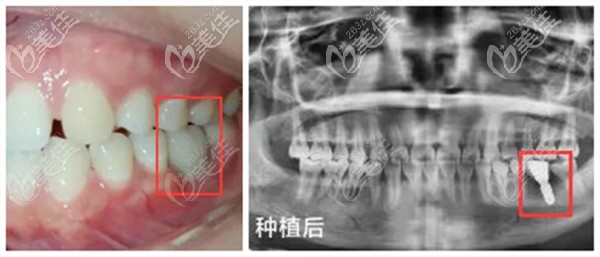

即刻种植技术:在拔牙后即刻植入种植体、安装基台、牙冠,当天就可以恢复咬合功能;不用像传统种植牙一样等3-6个月,也不用做二次手术。